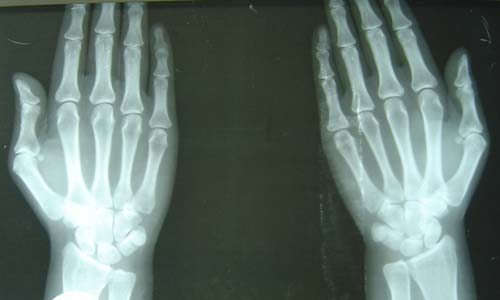

(图:来院时,患者双手肿胀,手指微变形)

X线检查:关节周围软组织肿胀,关节间隙狭窄,关节软骨组织遭到破坏,关节面毛糙。

两个疗程后,章女士双手关节肿胀僵硬全部消失,关节变形趋势得到控制,其他受累关节的肿胀疼痛均消失,腕部可以随意抬举,能够自己拿筷吃饭,不再需要家人的帮忙。离院前,主治医生利用HD-热层析检测系统检测章女士关节炎性介质的情况,发现炎性介质已全部被清除,X线检查显示双手骨质恢复正常,关节面光整,已达到临床 标准。

(图:X光显示患者双手骨质恢复正常,关节面光整)